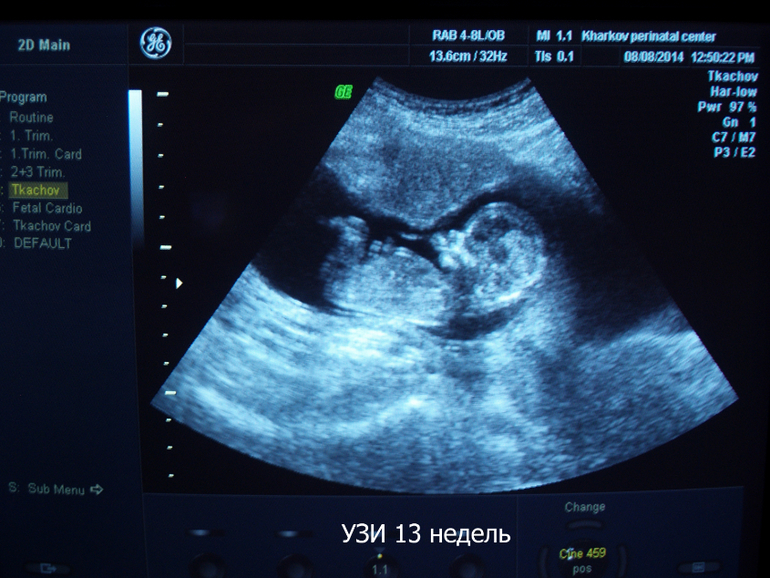

Мое узи в перинатальном в 13 и 20 нед